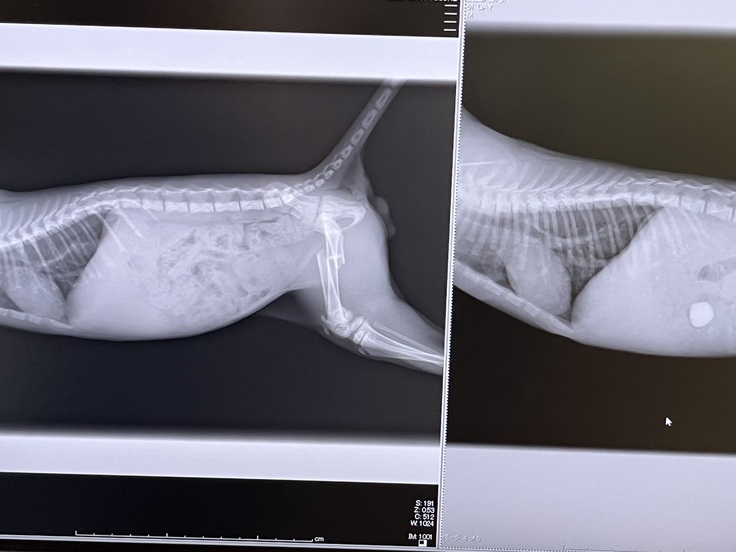

●2023/7/7

右は1週間前のレントゲンで、左が1週間後のレントゲン画像です。

砂利も小石もきれいに便と一緒に出たようで、お腹を切る必要はなくなりました!

あとは骨折の整復手術のみ...